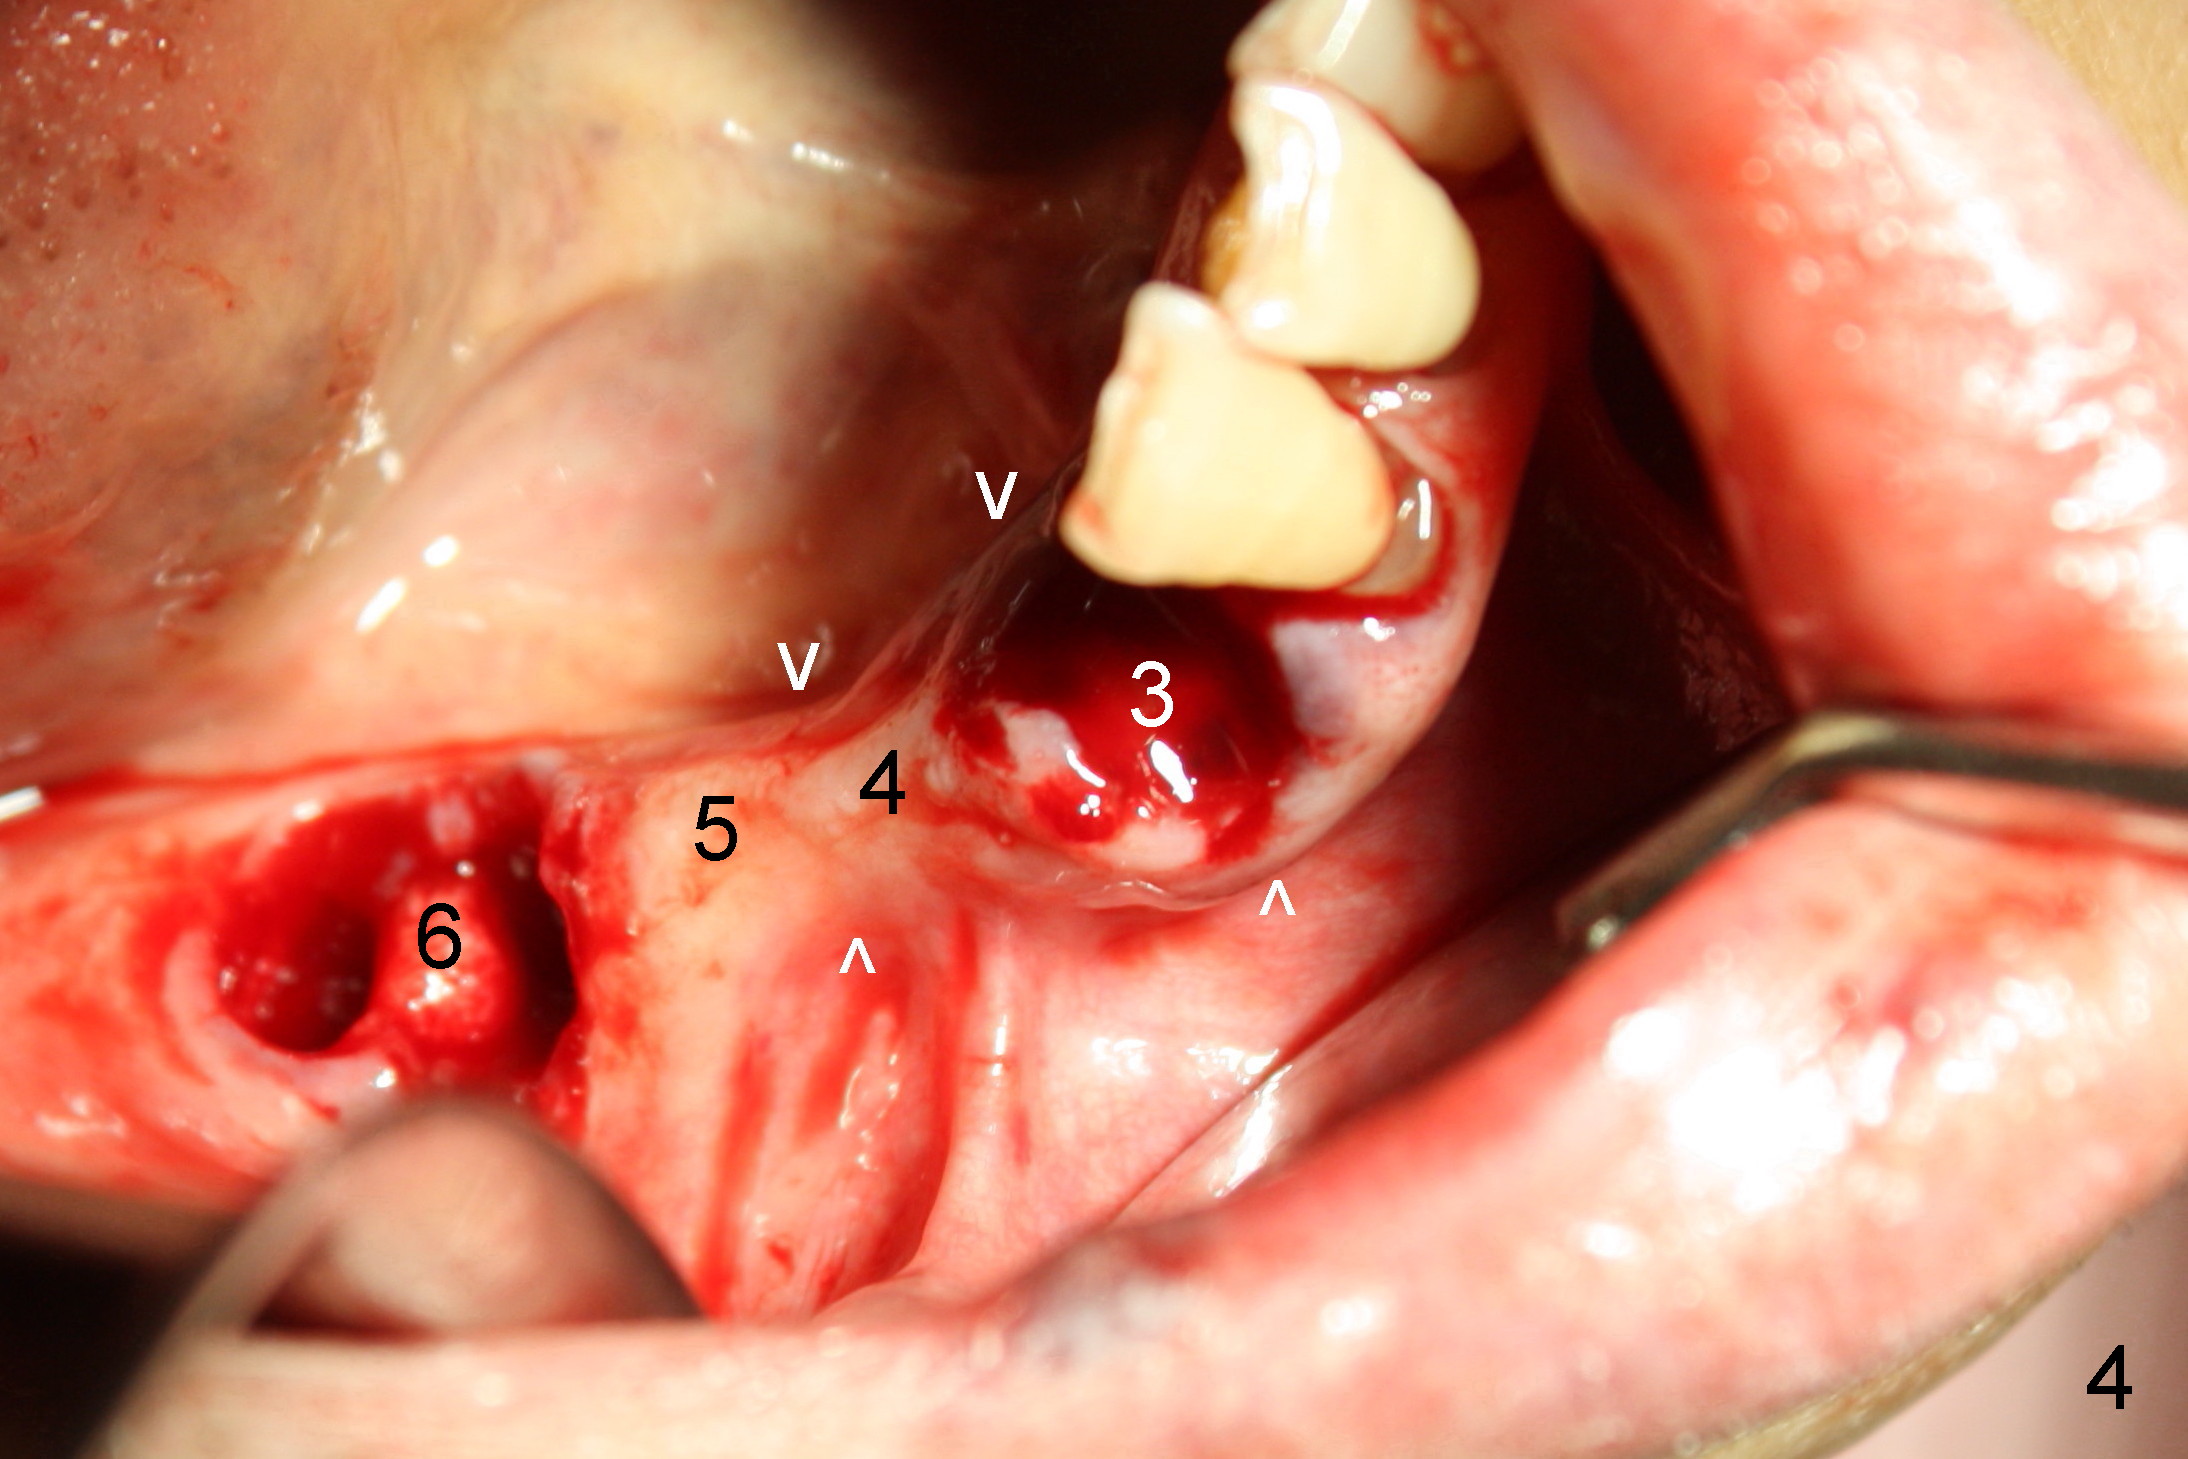

The lower right bridge (from canine (Fig.2: 3) to 1st molar (Fig.1: 6)) fails while a 77-year-old man is undergoing chemotherapy for urinary bladder cancer.  The abutments of the bridge are extracted without plan for implants (Fig.4).   Four months later, the patient returns for implants (Fig.3), but the ridge is narrow (Fig.5).  While 2 of 3x14 mm 1-piece implant are placed at the canine and 1st bicuspid sites, 2 piece ones at the 2nd bicuspid and 1st molar sites (Fig.6: 3.5x11 mm, 5x14 mm).  Soft (Fig.7-10) and hard (Fig.11) tissues heal 1 week (Fig.7) and 4 months (Fig.8-11).  There is minimal bone resorption 1 year 7 months post cementation (Fig.12,13, non-splinting).  It appears that narrow diameter implants are a valid solution to narrow ridge at the sites of the lower canine and premolar.  As long as there are enough implants for function, the crowns are not necessary to be splinted.  Surprisingly, the patient starts flossing after implant restoration.  Retrospectively an immediate provisional bridge should have been fabricated.